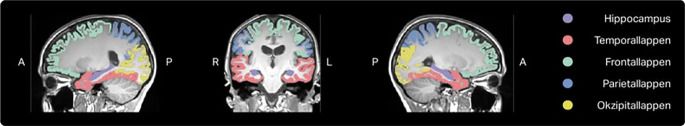

Methods: 10 healthy subjects (27.4 ± 1.71 years) were prospectively examined in a Philips Achieva 1.5T, Philips Ingenia CX 3T, Siemens MAGNETOM Aera 1.5T and Siemens MAGNETOM Vida 3T, the latter equipped with three different head coils, within one day. Brain volumetry of the whole brain, total white and grey matter, the cortical grey matter of the supratentorial lobes as well as regions important for the differentiation of neurodegenerative diseases of the dementia and movement disorder spectrum and the ventricular system was performed using the CE-certified software mdbrain by mediaire (Berlin, Germany). Both raw volumetry results and percentile allocation provided by the software were analysed.

Abstract Image